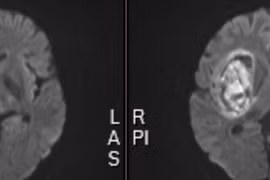

Đây là một ca máu tụ nội sọ kích thước và thể tích lớn trên nền bệnh nhân tăng huyết áp, béo phì... nếu không được phẫu thuật ngay hoặc quá trình vận chuyển không đảm bảo, tụt kẹt não dẫn đến tử vong.

Cả hai bệnh nhân đều trong tình trạng nguy kịch, rối loạn ý thức, huyết áp cao kịch ngưỡng. Dù bệnh nhân được cứu sống nhưng di chứng để lại vẫn rất nặng nề. Cần biết cách phòng tránh.